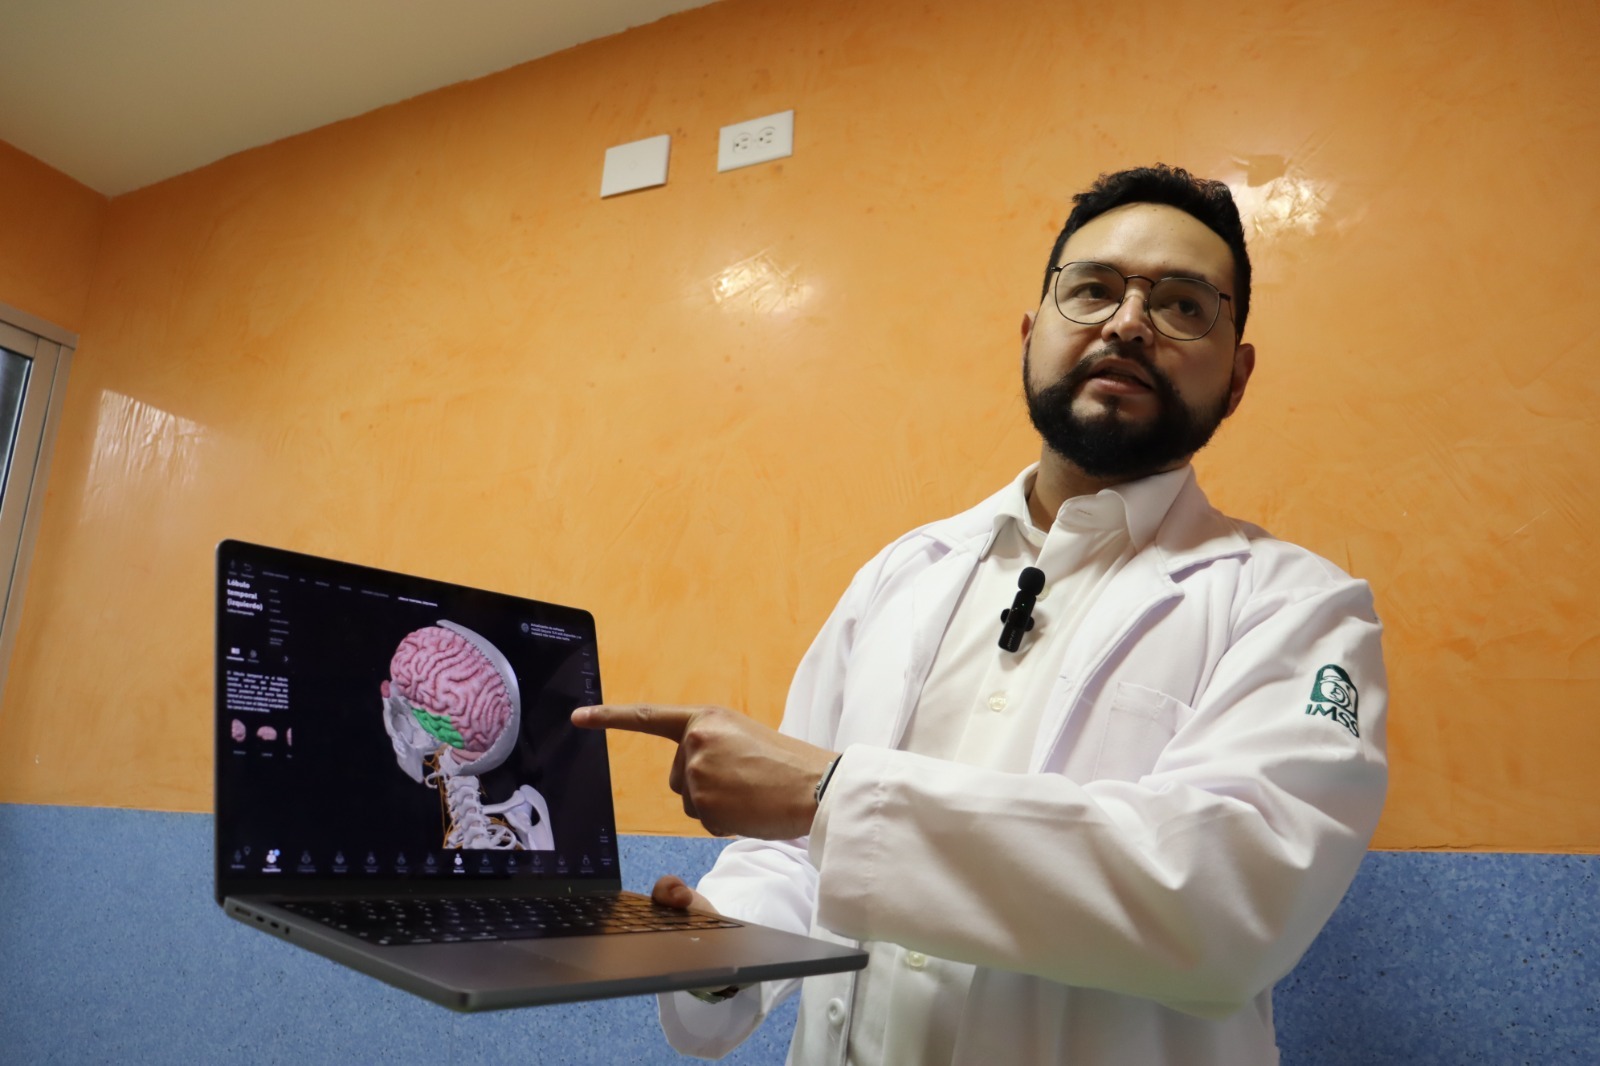

El procedimiento, encabezado por el neurocirujano pediatra doctor Gabriel Cachón Cámara, se llevó a cabo tras detectar un cavernoma, una lesión vascular compleja ubicada en una zona crítica del cerebro relacionada con el lenguaje y el movimiento. El joven Francisco, originario de Cancún, Quintana Roo, llegó a la UMAE después de sufrir crisis convulsivas, pérdida del conocimiento y dificultades para hablar y moverse.

Durante la cirugía, el equipo de anestesiólogos aplicó la técnica “despierto-dormido-despierto”, que permitió mantener al paciente consciente en etapas clave de la intervención. Con apoyo de un sistema de navegación cerebral tipo GPS, los especialistas pudieron localizar el tumor con precisión y retirarlo totalmente, preservando las funciones motoras y del lenguaje del adolescente.

El doctor Roberto Abraham Betancourt, director de la UMAE en Mérida, destacó que esta primera neurocirugía con paciente pediátrico despierto representa un hito médico en Yucatán y refrenda el compromiso del IMSS con la atención médica de alta especialidad y con el bienestar de la población derechohabiente.